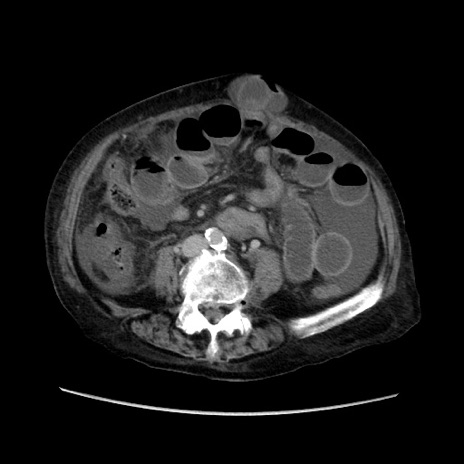

症例31(横断像)

【症例】80歳代 女性

【主訴】腹部膨満感

【現病歴】他院にて肝硬変にてフォロー中。1週間前から便秘、腹部膨満感、臍部腫瘤あり受診となる。

【既往歴】肝硬変

【身体所見】腹部膨隆あり、皮膚変化なし、疼痛なし。

【データ】WBC 4600、CRP 0.25